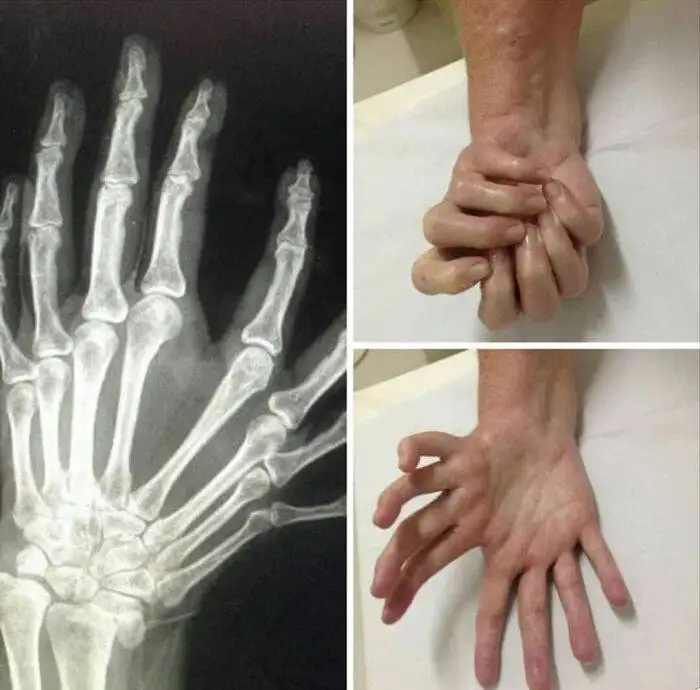

مورد نادری از ناهنجاری شستِ ترایفلنجیل

در این تصاویر نمونه ای از یک ناهنجاری مادرزادی نادر به نام Triphalangeal Thumb(یا شستِ سه بندی که در آن انگشت شست فرد بند یا بندهای اضافه دارد) را مشاهده می کنید. این ناهنجاری به صورت نزمال در هر 25 هزار نوزاد زنده، یک بار اتفاق می افتد و در دو سوم از موارد ثبت شده این ناهنجاری در خانواده فرد سابقه داشته است.